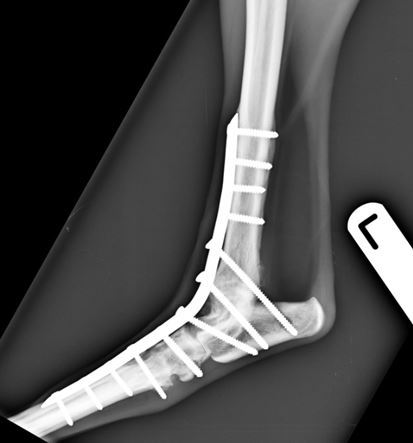

A craniomedial approach to the hock joint was made and upon inspection of the fracture site it was evident that it would not be possible to reconstruct and repair the talar fracture. A decision was therefore made to perform a pantarsal arthrodesis using a specifically designed dorsal pantarsal arthrodesis plate. The plate features 3.5mm screws in the proximal part of the plate and 2.7mm screws distally in the metatarsal. This provides an extremely rigid stable fixation. Cartilage was removed using a high speed burr from the articular surfaces. The fractured parts of the talus were morselised, mixed with further cancellous bone graft taken from the proximal tibia and demineralised bone matrix and used to fill the joints spaces. The plate was applied and the skin closed routinely.

She made a good recovery from the anaesthetic and no further problems were seen during recuperation. The excellent biomechanical stability of the repair meant that a cast was not needed post-operatively, avoiding cast associated complications.

Figure 3. Six-weeks post-operative lateral view